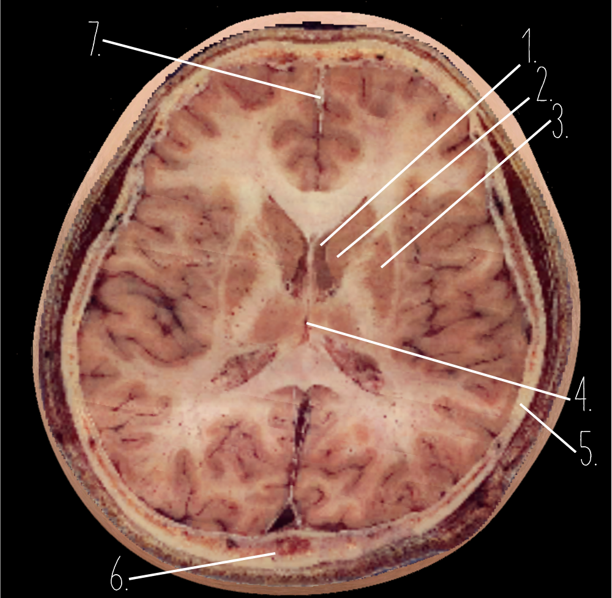

1?

Temporal Bone

2?

Occipital Lobe

3?

Straight Sinus

4?

Body of corpus callosum

5?

Superior Sagittal Sinus

1?

Choroid Plexus

2?

Lateral Ventricle

3?

Caudate Nucleus

4?

Third Ventricle

5?

Parietal Bone

6?

Occipital Bone

7?

Falx Cerebri